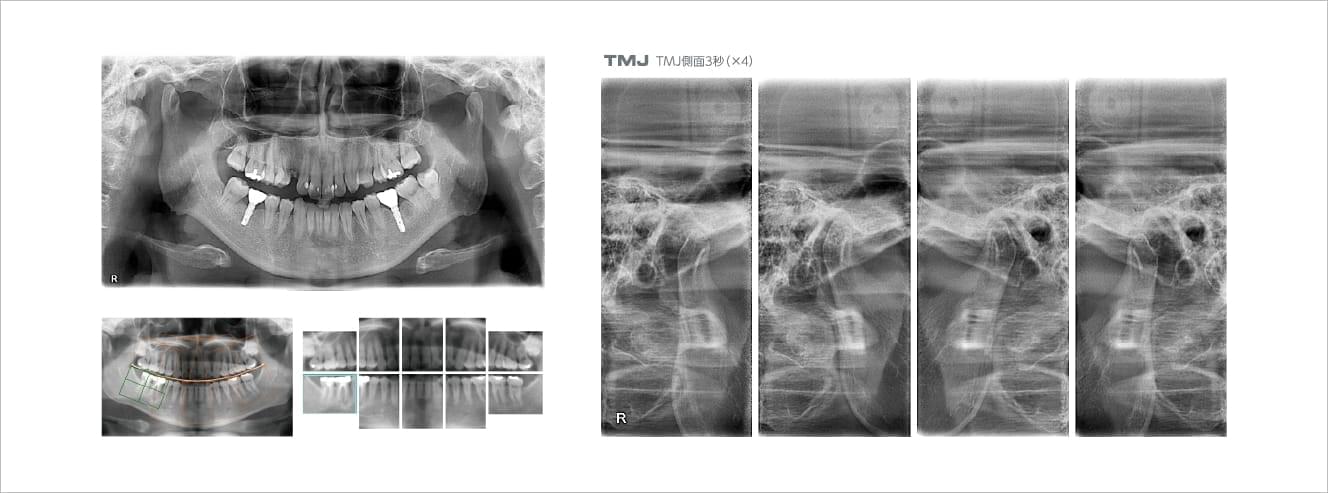

デンタルエックス線写真 SOLIO XZⅡ / SOLIO XZⅡMAXIM | X線撮影装置 | タカラの詳細情報

SOLIO XZⅡ / SOLIO XZⅡMAXIM | X線撮影装置 | タカラ。◇デジタルCMOSセンサー EzSensor Soft サイズ2.0 (25.9×35.9mm。歯科用X線装置選定ガイド - 朝日レントゲン工業株式会社。デンタルエックス線写真斉田 寛之クインテッセンス出版書き込み等もなく比較的綺麗な方かと思います。歯科用X線撮影 - 米沢市立病院。